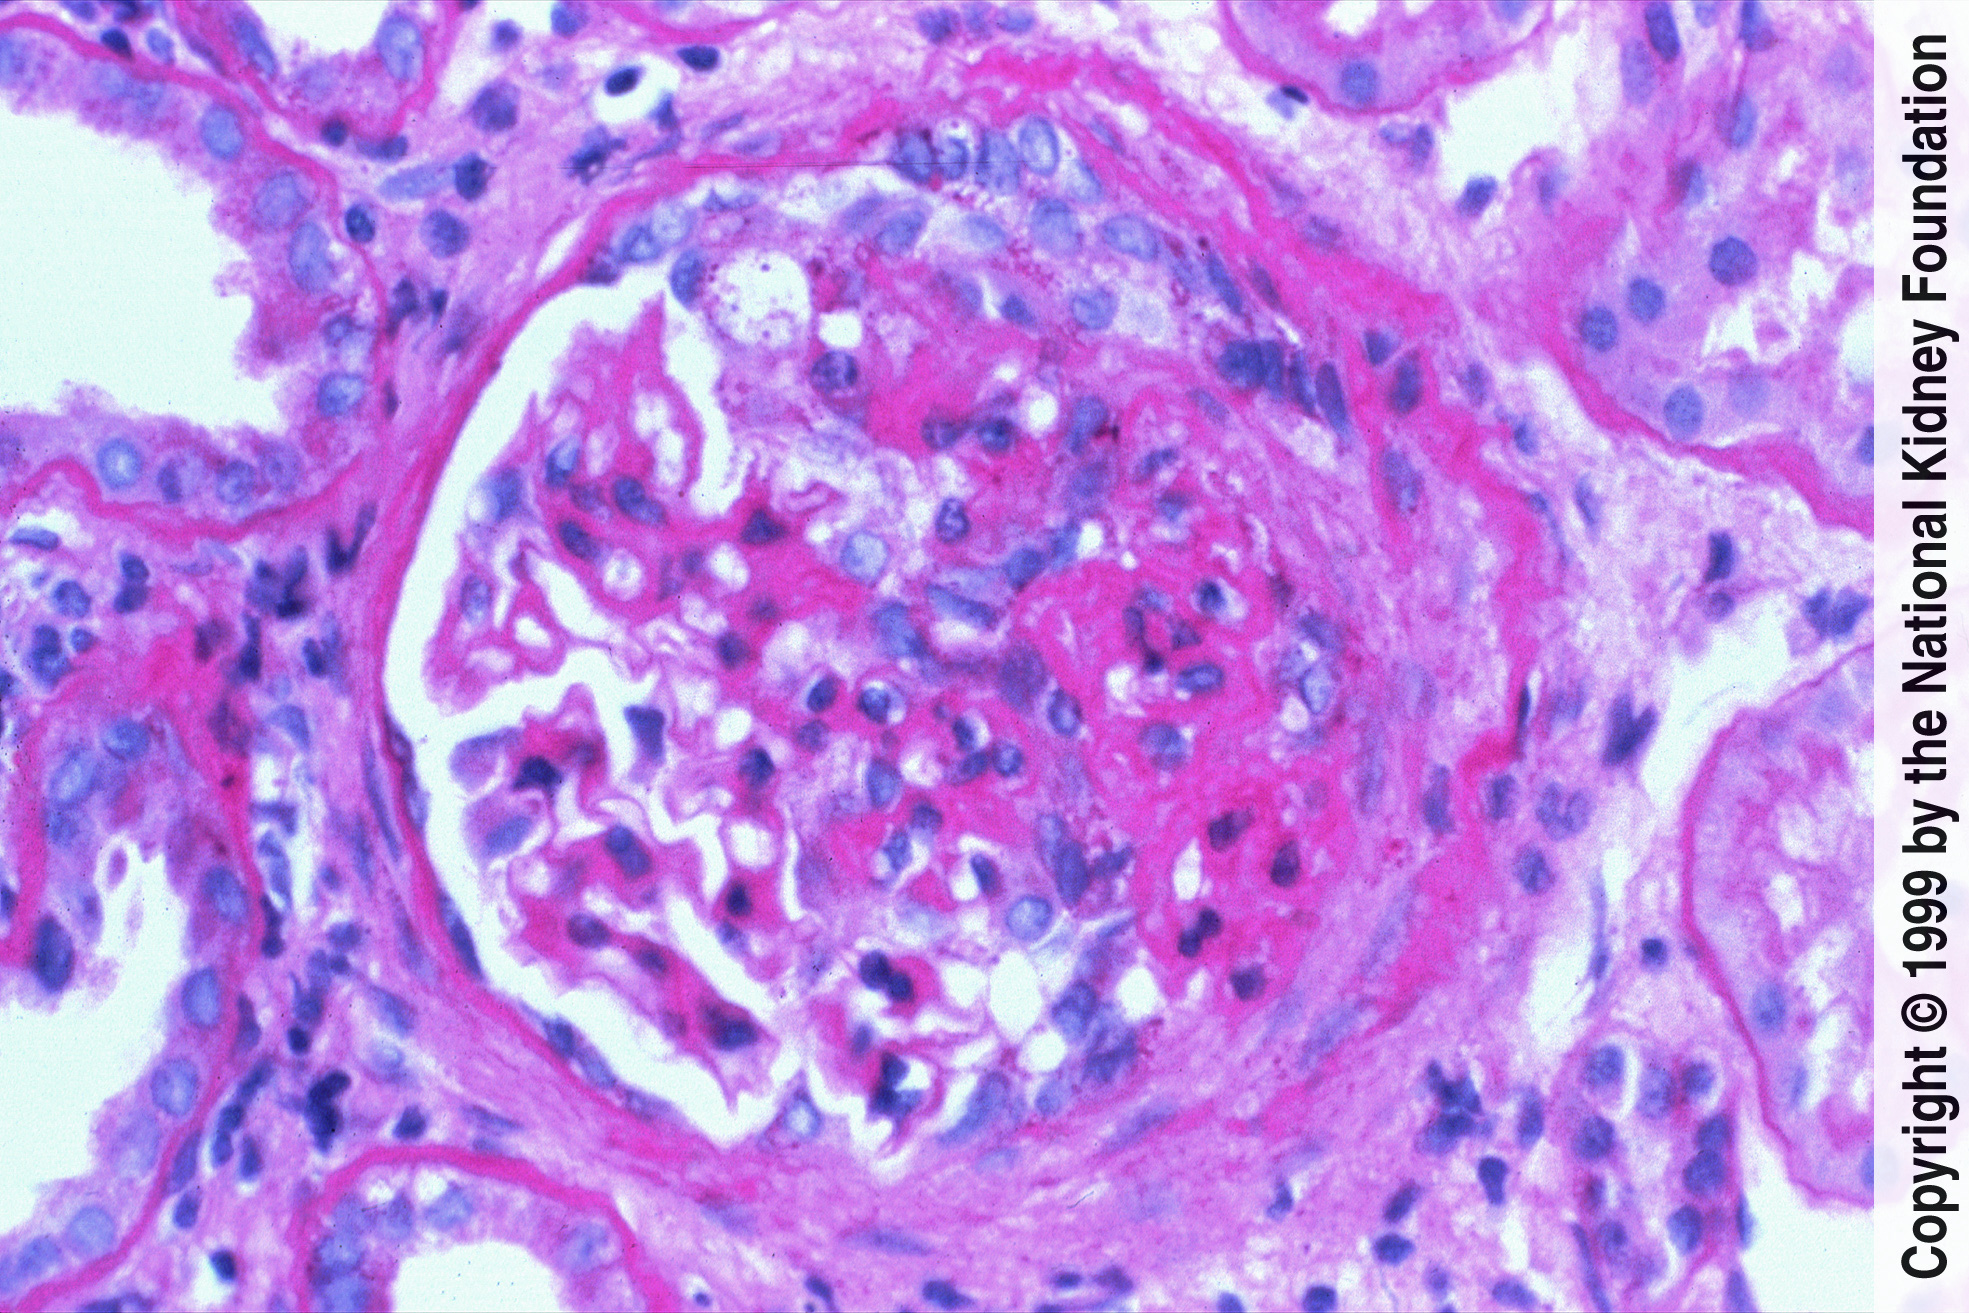

Program je zasnovan kot poglobljen in praktično usmerjen pregled: od prepoznave na primarni ravni in pravilne napotitve v nefrološko obravnavo do razumevanja patofiziologije, diagnostike in aktualnih terapevtskih pristopov. Obravnavali bomo ključne glomerulne bolezni (npr. IgA glomerulonefritis, podocitopatije, sistemske vaskulitise, s komplementom povezane glomerulne bolezni ipd.) ter obravnavo v posebnih stanjih (nosečnost, dializa, presaditev ledvice). Predstavili bomo tudi sistematično zbrane izkušnje UKC Ljubljana pri posameznih boleznih v obdobju 10 let in več.

Šola glomerulnih bolezni je namenjena specialistom in specializantom vseh specialnosti, ki v klinični praksi obravnavajo bolnike z glomerulno boleznijo ali s sistemsko avtoimunsko boleznijo z ledvično prizadetostjo – prvenstveno nefrologom, revmatologom in družinskim zdravnikom, pa tudi vsem zdravnikom, ki želijo pridobiti ali nadgraditi znanje o glomerulnih boleznih ter se seznaniti s sodobnim pristopom k bolniku z glomerulonefritisom.